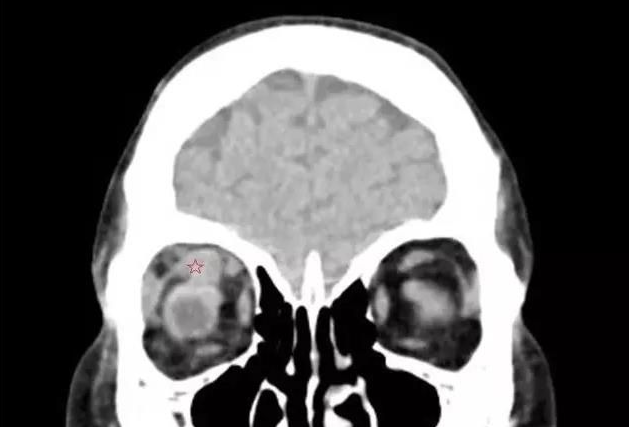

甲状腺相关眼病,是眼科较常见的疾病之一 。其包括:眼球突出、复视等,对患者的生活和工作带来极大的不便。

来自泉州南安的刘先生发现自己的眼睛莫名的越来越突,还容易流眼泪,转动不灵活,看东西模糊,一个东西变成两个,看马路上的车一辆变成两辆,上下楼梯也踩不准,并且脾气变得暴躁。在当地医生的建议下,今年4月,刘先生又来到了厦门眼科中心斜视与小儿眼科检查,谢仁艺副主任医师在询问了解了刘先生的病情后,并结合各项检查报告判定刘先生是患了甲状腺相关眼病。

谢仁艺副主任医师介绍,刘先生眼睛病变是因甲亢引起,导致双眼眼外肌发炎、肿胀、变性、纤维化, 终失去弹性,这也是他眼球转动不灵活引起斜视、复视的主要原因。